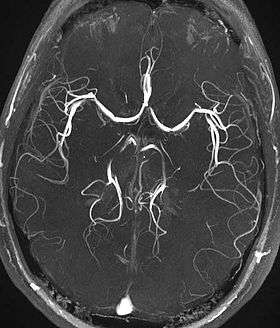

Time-of-flight MRA at the level of the Circle of Willis.

Time-of-flight (TOF) or inflow angiography, uses a short echo time and flow compensation to make flowing blood much brighter than stationary tissue. As flowing blood enters the area being imaged it has seen a limited number of excitation pulses so it is not saturated, this gives it a much higher signal than the saturated stationary tissue. As this method is dependent on flowing blood, areas with slow flow (such as large aneurysms) or flow that is in plane of the image may not be well visualized. This is most commonly used in the head and neck and gives detailed high-resolution images.